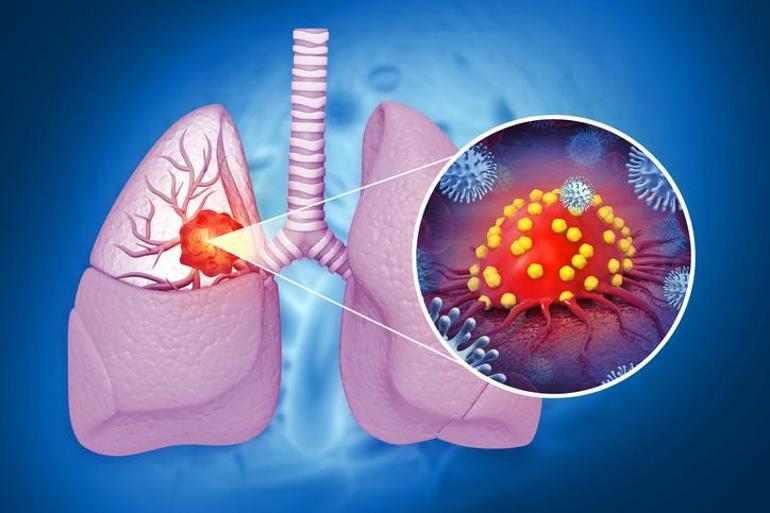

En önemli sağlık hastalıkları arasında yer alan pulmoner kanser, bir dizi semptomun ardından kendini gösterir. Özellikle sağlık temelli sağlık sorunları alanında da belirtiler vardır. Aynı zamanda, bu semptomlar birden fazla meydana geldiğinde, bir doktora danışmak gerekir.

Yukarıda belirtilen farklı semptomlar akciğer kanseri çatışmasını ortaya çıkarabilir. Özellikle öksürük sırasında kan acil veya ciddi kilo kaybı önemli semptomlar arasındadır.

Akciğer kanserini anlamak için semptomlar ilk kez tartışılır. Bu semptomlar, kişiden başlayarak uzman doktorun kontrolü altındaki ön muayene ile sağlanır. Zayıflık, yorgunluk, öksürük anında kanı, kilo kaybı ve iştah kaybı gibi birçok semptom ön plana çıkar. Bu işlemin ardından, prosedür görüntüleme yöntemleri göz önüne alındığında kesin tanı için uygulanır.